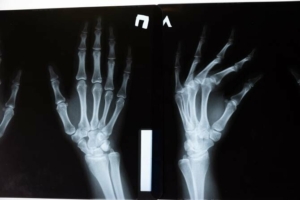

NFT-botrány: Egy orvos NFT-ként árulta a terrortámadásban meglőtt nő röntgenképét

Bíróság elé áll az az orvos, aki digitális műalkotásnak címkézve kezdte el NFT-ként árulni annak a páciensének a röntgenképét, aki a 2015-ös francia terrortámadásban megsérült. A BBC szerint a párizsi … Bővebben: NFT-botrány: Egy orvos NFT-ként árulta a terrortámadásban meglőtt nő röntgenképét